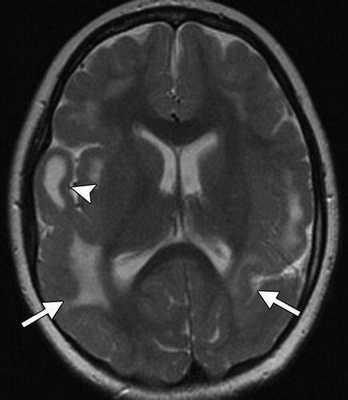

• Ранние изменения: гиперинтенсивный на Т2-ВИ сигнал (отек, некроз нейронов), вовлечение БГ в 57% случаев

(а) Бесконтрастная КТ, аксиальный срез: у новорожденного с ВПГ-2-энцефалитом определяются протяженные зоны снижения плотности серого и белого вещества. У 27% инфицированных новорожденных признаков заболевания при первичной бесконтрастной КТ не наблюдается.

С рождения наблюдалась везикулезная сыпь в области лба. На аксиальной Т2-взвешенной томограмме определяется «missing cortex» симптом: потеря нормального изменения сигнала от коры (кора и белое вещество неразличимы) в обеих затылочных областях, больше слева.